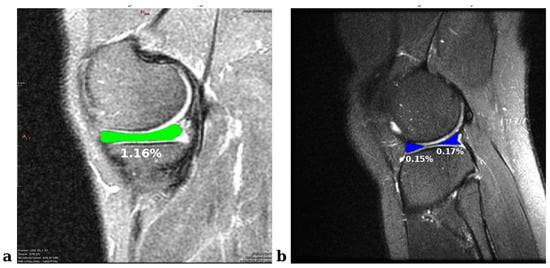

This study aims to extract meniscal ROIs from knee MRI images and improve segmentation results using ensemble-based approaches. We trained segmentation models based on state-of-the-art YOLO versions. We optimized the results using innovative ensemble methods such as pixel-based voting, weighted multiple voting, and dynamic weighted multiple voting with grid search. Meniscal volume is known to be less than 0.1% of the entire knee joint MRI scan [35] and, in the 2D images used in this study, meniscal ROI areas represent less than 1.5% (Figure 7). The manual segmentation of such small tissues has limited applicability due to its high risk of error and time-consuming nature. Therefore, deep learning-based approaches offer practical solutions to overcome these challenges. Furthermore, this is the first known study in which segmentation models based on the YOLO series are integrated with innovative ensemble methods (e.g., grid-search-based dynamic weighting) to improve performance.

Figure 7. An example of knee MRI images that represent the sizes of meniscal ROI areas. (a) Medial meniscus with meniscal tear in the internal set. (b) Healthy lateral meniscus in the external set.